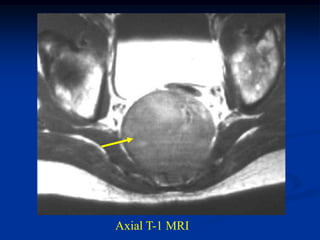

Case #1105

54 year male with

chordoma C-spine